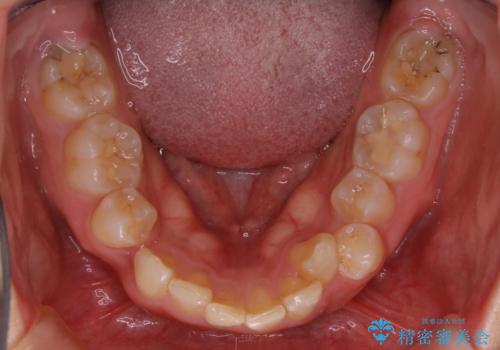

また、右下の歯が生まれつき少なく、隙間が空いている状態でした。

矯正治療でご自身の歯を移動して閉じることにしました。

また、咬んだときに下の前歯が隠れる過蓋咬合でしたが、矯正治療で改善しました。